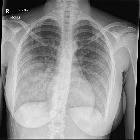

Plain radiograph

The clinical context is crucial in image interpretation. The exact pattern may differ depending on the underlying cause. In general, the typical feature on plain film during an acute diffuse alveolar hemorrhage is a diffuse infiltrative opacification pattern . At times there may a slight predilection towards the mid zones with some apical sparing .